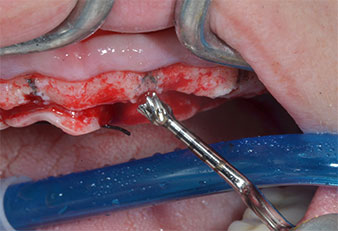

Uno strumento piezoelettrico (Piezomed I1) a forma di fiamma, rivestito in diamante, è stato usato per contrassegnare le posizioni dell'impianto e per eseguire una preparazione pilota (Fig. 3). Si è prestato attenzione a utilizzare un movimento verticale ascendente e discendente, con potenza ridotta, irrigazione completa e bassa pressione (inferiore a 300 g). Successivamente è stato applicato uno strumento pilota (Piezomed I2A/I2P) per l'ingrandimento iniziale delle sedi dell'impianto del diametro di 2 mm (Fig. 4), seguito da un inserto da 3 mm (Fig. 5).

Strumento marcatore a ultrasuoni Piezomed

Fig. 3: la preparazione con lo strumento marcatore a ultrasuoni Piezomed I1 viene eseguita in un movimento verticale ascendente e discendente, parallelo all'asse longitudinale della parte lavorante.